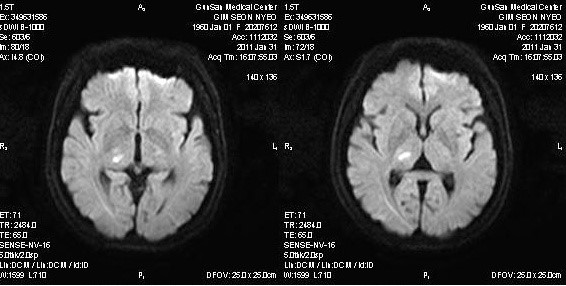

头颅MRI:右侧丘脑梗死(图1)。

图1 头颅MRI DWI像显示右侧丘脑梗死(来自网络课件,中山大学彭福华教授病例)